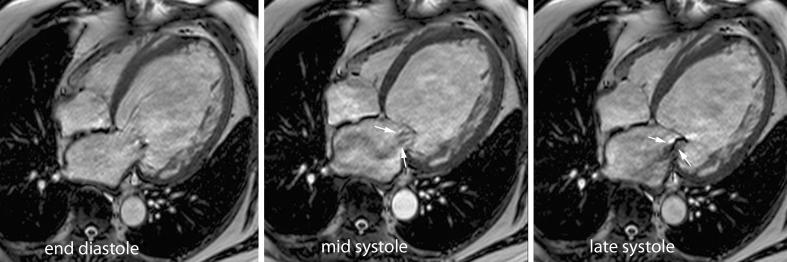

The emerging role of magnetic resonance imaging and multidetector computed tomography in the diagnosis of dilated cardiomyopathy.

Magnetic resonance imaging and multidetector computed tomography are new imaging methods that have much to offer clinicians caring for patients with dilated cardiomyopathy. In this article we briefly describe the clinical, pathophysiological and histological aspects of dilated cardiomyopathy. Then we discuss in detail the use of both imaging methods for measurement of chamber size, global and regional function, for myocardial tissue characterisation, including myocardial viability assessment, and determination of arrhythmogenic substrate, and their emerging role in cardiac resynchronisation therapy. ELECTRONIC SUPPLEMENTARY MATERIAL: The online version of this article (doi:10.1007/s13244-011-0101-8) contains supplementary material, which is available to authorized users.